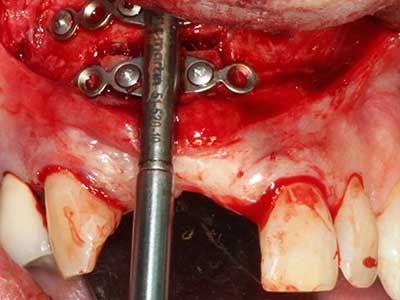

Bone tissue is not simply a mineral structure but also contains a substantial proportion of collagen fibres. This means it not only has good compressive strength but also a degree of flexibility, which can be taken advantage of when performing bone augmentations. In the classical expansion procedure using bone splitting, the atrophied alveolar ridge is split longitudinally and carefully expanded after reaching an adequate osteotomy depth (Fig. 13-16), ideally without substantial removal of the periosteum (Brugnami, Caiazzo et al. 2014, Stricker, Fleiner et al. 2014). Screw and plate systems with increasing expansion distance have proven effective in separating the two bone lamellae while remaining below the fracture threshold. In general, residual bone widths of at least 3–4 mm are required (Chiapasco, Zaniboni et al. 2006) to guarantee adequate flexibility and sufficient bone coverage of the future implants. If necessary, a vertical relief osteotomy on one or both sides can improve flexibility. A combination with additional augmentation techniques, particularly on the buccal side, has been described as an alternative to the classical technique.

The splitting procedure is particularly atraumatic and there is no significant loss of dimension when using piezosaws, and there are no significant differences between implants in split jaws and implants in an alveolar ridge without a bone deficit (Chiapasco, Zaniboni et al. 2006, Danza, Guidi et al. 2009). However, sufficient continuous irrigation is essential, particularly with locally restricted and deep splitting to prevent thermal stress in the apical osteotomy regions.